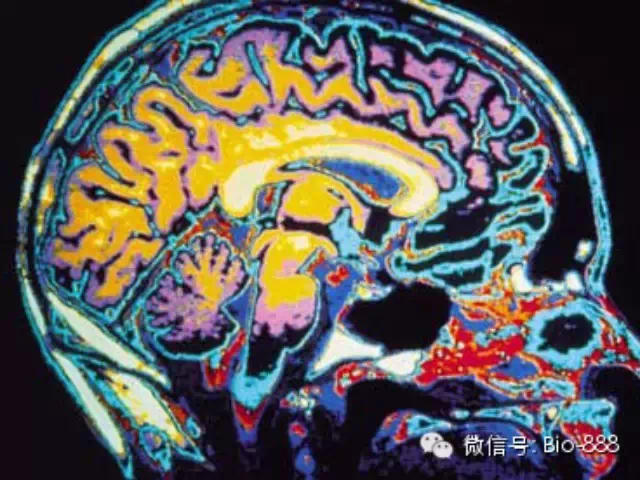

自古以来,预测未来运势一直是人类孜孜以求的目标。从殷商的龟甲兽骨到今日的星座血型,人类似乎从来没有放弃过这个几乎不可能的任务。不过可惜的是,迄今为止还没有任何一种理论或技术可以真正做到预测未来。然而最近,来自麻省理工学院脑与认知科学系的约翰·加布里埃利(John  D.E. Gabrieli)教授撰文指出,基于如核磁共振成像(MRI)等的新一代无创神经成像技术(noninvasive  neuroimaging)可能为预测个人未来行为趋势提供新的参考。这篇综述今天发表在《神经元》(Neuron)上。

到了20世纪后半叶,由于物理学的进步,许多新的研究手段被开发出来,神经科学家们从此终于可以不用开颅也能知道大脑的信息了。其中,基于“核磁共振”原理所制造的核磁共振成像系统(MRI)可以像X光或是CT扫描一样“透视”大脑,同时还比它们拥有更高的分辨率且不会产生任何伤害。MRI目前已世界主流神经科学或心理学研究机构的标准配置。

加布里埃利认为,这种高性能的设备可以从人类大脑当中分析出海量的数据,结合现代的超级计算机与大数据算法,就可以借助这些数据对具体个人在未来一段时间内的心理、健康乃至行为作出预测,从而实现个性化的医疗、教育和生活指导。